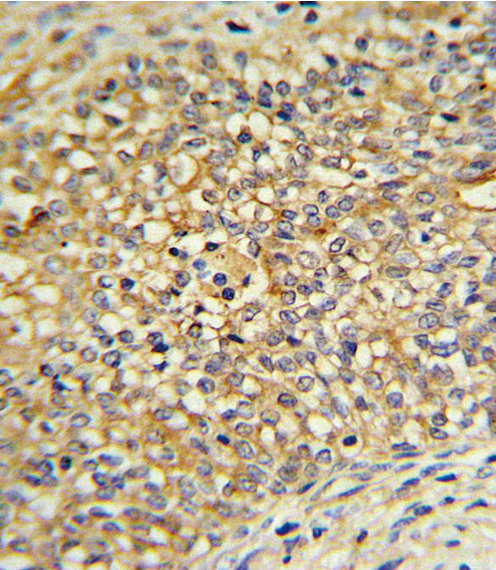

Product Image

- UDB17 Antibody (Center) (Cat.# P30374) IHC analysis in formalin fixed and paraffin embedded human Prostate carcinoma followed by peroxidase conjugation of the secondary antibody and DAB staining. This data demonstrates the use of the UDB17 Antibody (Center) for immunohistochemistry. Clinical relevance has not been evaluated.